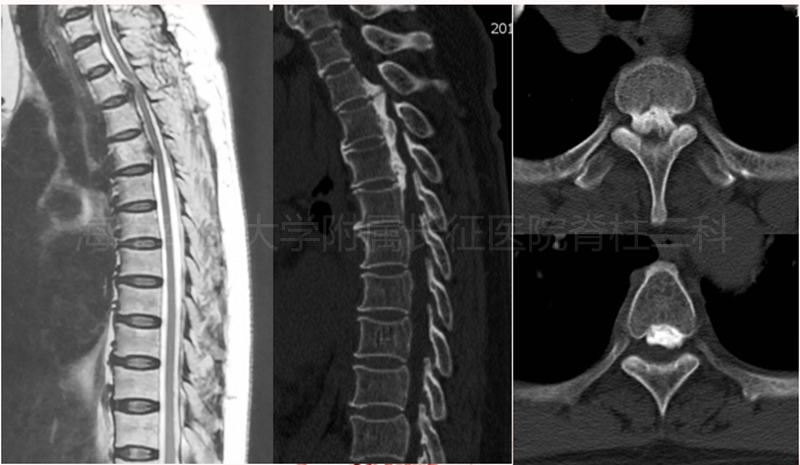

术前侧位平片和矢状位、水平位CT

术前矢状位、水平位MRI